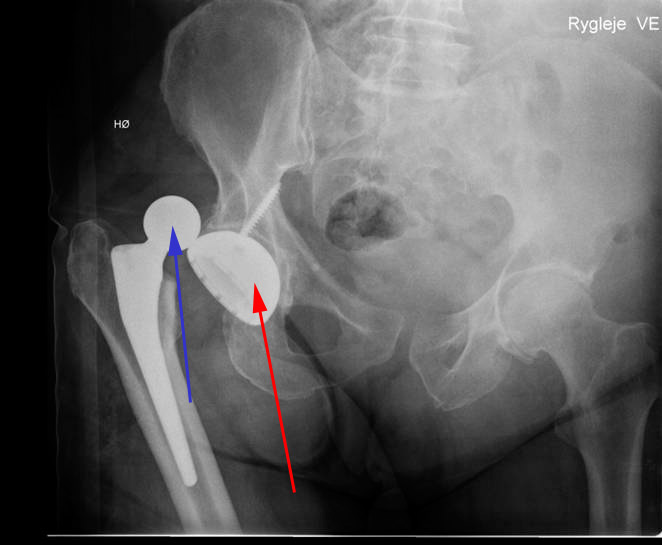

Hofte, proteseluksation, røntgen

Patient med fuld hofteprotese. Røntgenbilledet viser, at protesen er gået af led. Det kunstige ledhoved (blå pil) er gledet bagud af den kunstige hofteskål (rød pil).